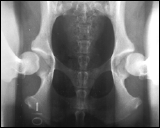

2. Kompression

Die Lagerung erfolgt wie in 1, nur werden diesmal die Gelenkköpfe des Femurs sanft in die Gelenkpfanne positioniert.

In dieser Ansicht können pathologische Veränderungen am Gelenk identifiziert werden. Ebenso ist es möglich zu prüfen, wie akurat der Gelenkkopf in die Gelenkpfanne passt.